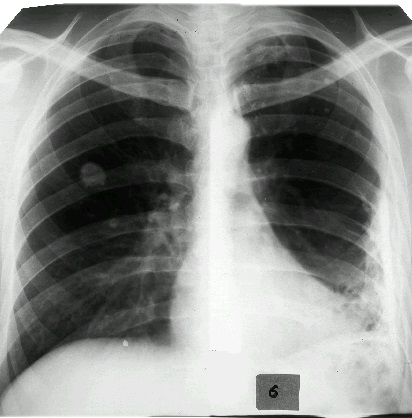

Наряду с клиническими проявлениями экссудативного плеврита при осмотре пациента выявляется асимметрия грудной клетки, выбухание межреберных промежутков на соответствующей половине грудной клетки, отставание пораженной стороны при дыхании. Перкуторный звук над экссудатом притуплен, бронхофония и голосовое дрожание ослаблены, дыхание слабое или не выслушивается. Верхняя граница выпота определяется перкуторно, при рентгенографии легких или при помощи УЗИ плевральной полости.